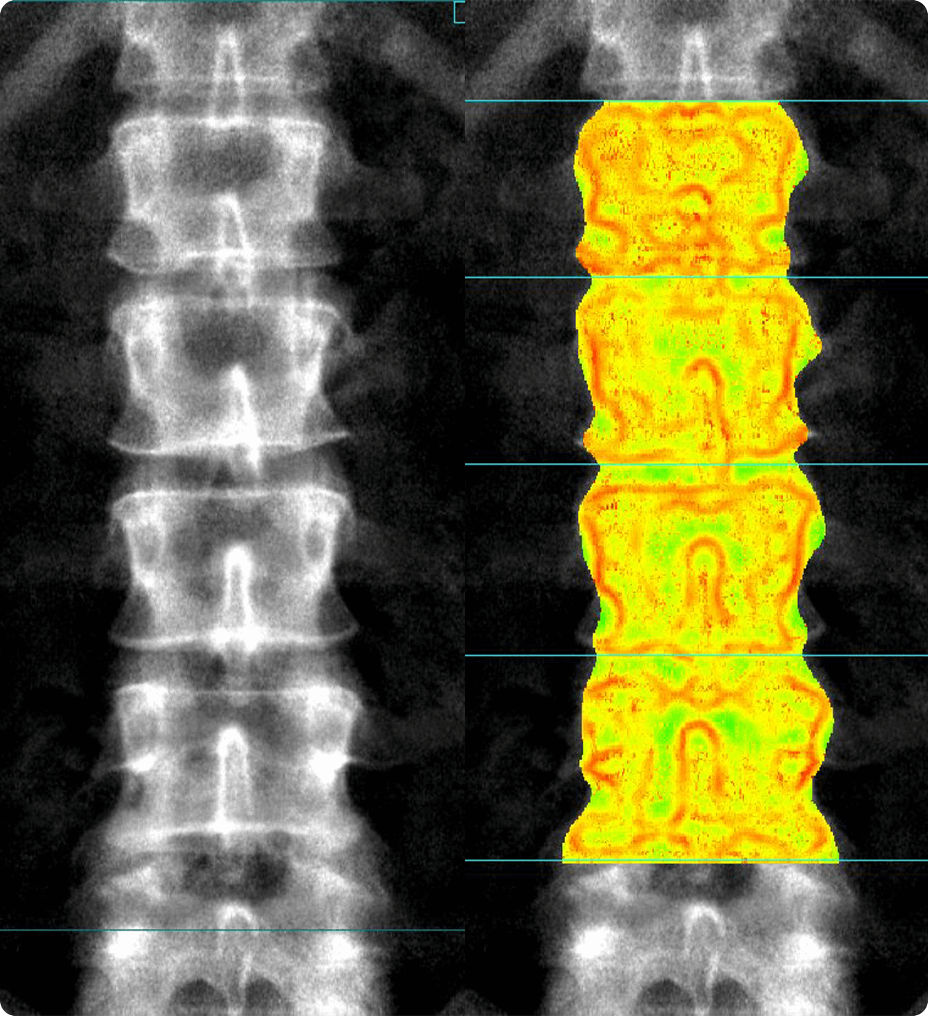

Integrated Trabecular Bone Score

TBS is a separate risk factor from bone density that measures bone quality and research suggests that it adds to DXA in predicting patients:

• A skeletal status assessment table was added, providing a “Bone Resilience Index” that visually shows the combined BMD T-score and TBS categories.

• New therapeutic decision tools have been introduced, including TBS adjusted FRAX® and TBS adjusted BMD T-score. These tools can be helpful since different drugs may impact bone density and bone micro-architecture differently.

• For quicker workflow, automated conclusions are now included in the report, providing conclusions based on medical society guidelines.